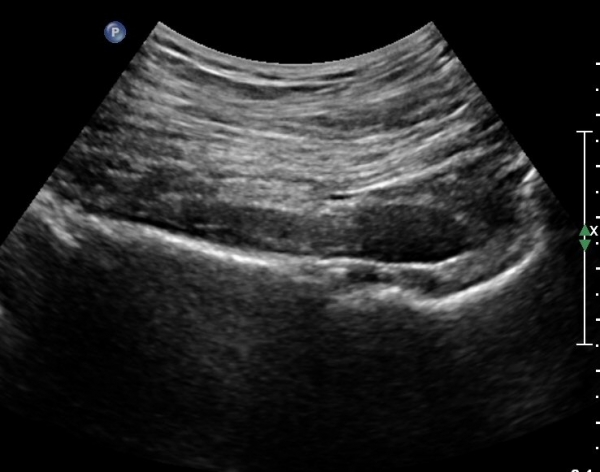

ŽÃÍÀÚ¸¦ ´Ù¸®ÂÊÀ¸·Î ¼öÆò À̵¿ÇÏ¸é ½ÉÃþ¿¡¼­ Àå°ñÀÌ »ç¶óÁö°í »õ·Î¿î ±ÙÀ°ÃþÀÌ º¸À̴µ¥ À̰ÍÀÌ ÀÌ»ó±ÙÀ̰í ÀÌ»ç±Ù ½ÉÃþ¿¡¼­ Á°ñ½Å°æ¸£ °üÂûÇÒ ¼ö ÀÖ´Ù(»çÁø 2, 3).